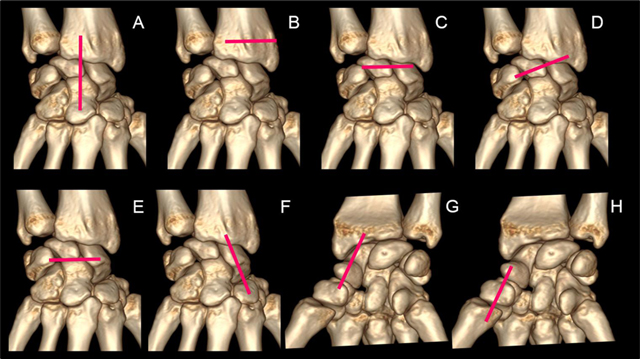

Figure 8

A 7-step standardized US examination framework for wrist injuries: (A) sagittal view of the carpal bones along the long-axis of the third ray. (B) localization of the Lister tubercle. (C) axial view of the dorsal band of the scapholunate ligament. (D) axial oblique view of the radiolunotriquetral ligament. (E) Axial view of the scapholunotriquetral ligament. (F) sagittal view of the dorsal cortex of the scaphoid with the wrist in ulnar deviation. (G) sagittal view of the palmar cortex of the scaphoid with the wrist in ulnar deviation. (H) sagittal view of the first ray (palmar aspect).